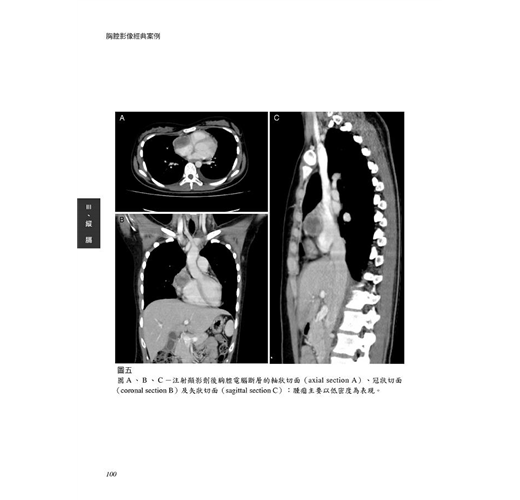

病例23 血管肉瘤(Angiosarcoma) 98